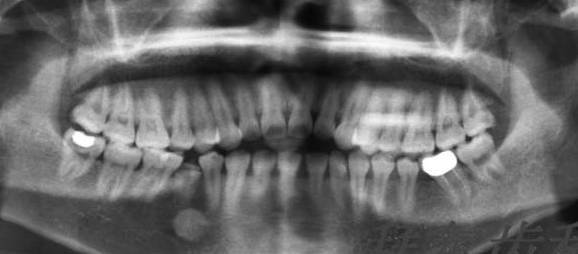

拍片、制模

首先需要拍片牙齿头部骨头的照片以便能看见牙齿骨骼的发展方向,方便以后制定合适的矫正方案,以后好制膜备用。